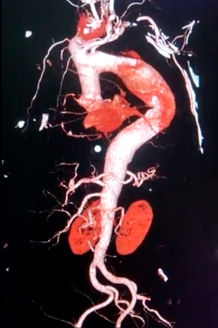

Dilatación segmentaria significativa de un trayecto vascular ( arterial o venoso) con riesgos de roptura y puede provocar la muerte.